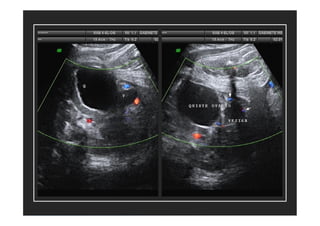

• Quistes de ovario

1ª causa de quiste abdominal en feto mujer

Aparecen en 3º T y la mayoría son benignos

Eco: formación anecoica en parte inferior del

abdomen, gen. unilateral y unilocular.

Conducta expectante con controles eco

mensuales

Pronóstico: involución espontánea

intraútero o postparto

Otras anomalías • Quistesde ovario 1ª causa de quiste abdominal en feto mujer Aparecen en 3º T y la mayoría son benignos Eco: formación anecoica en parte inferior del abdomen, gen. unilateral y unilocular. Conducta expectante con controles eco mensuales Pronóstico: involución espontánea intraútero o postparto